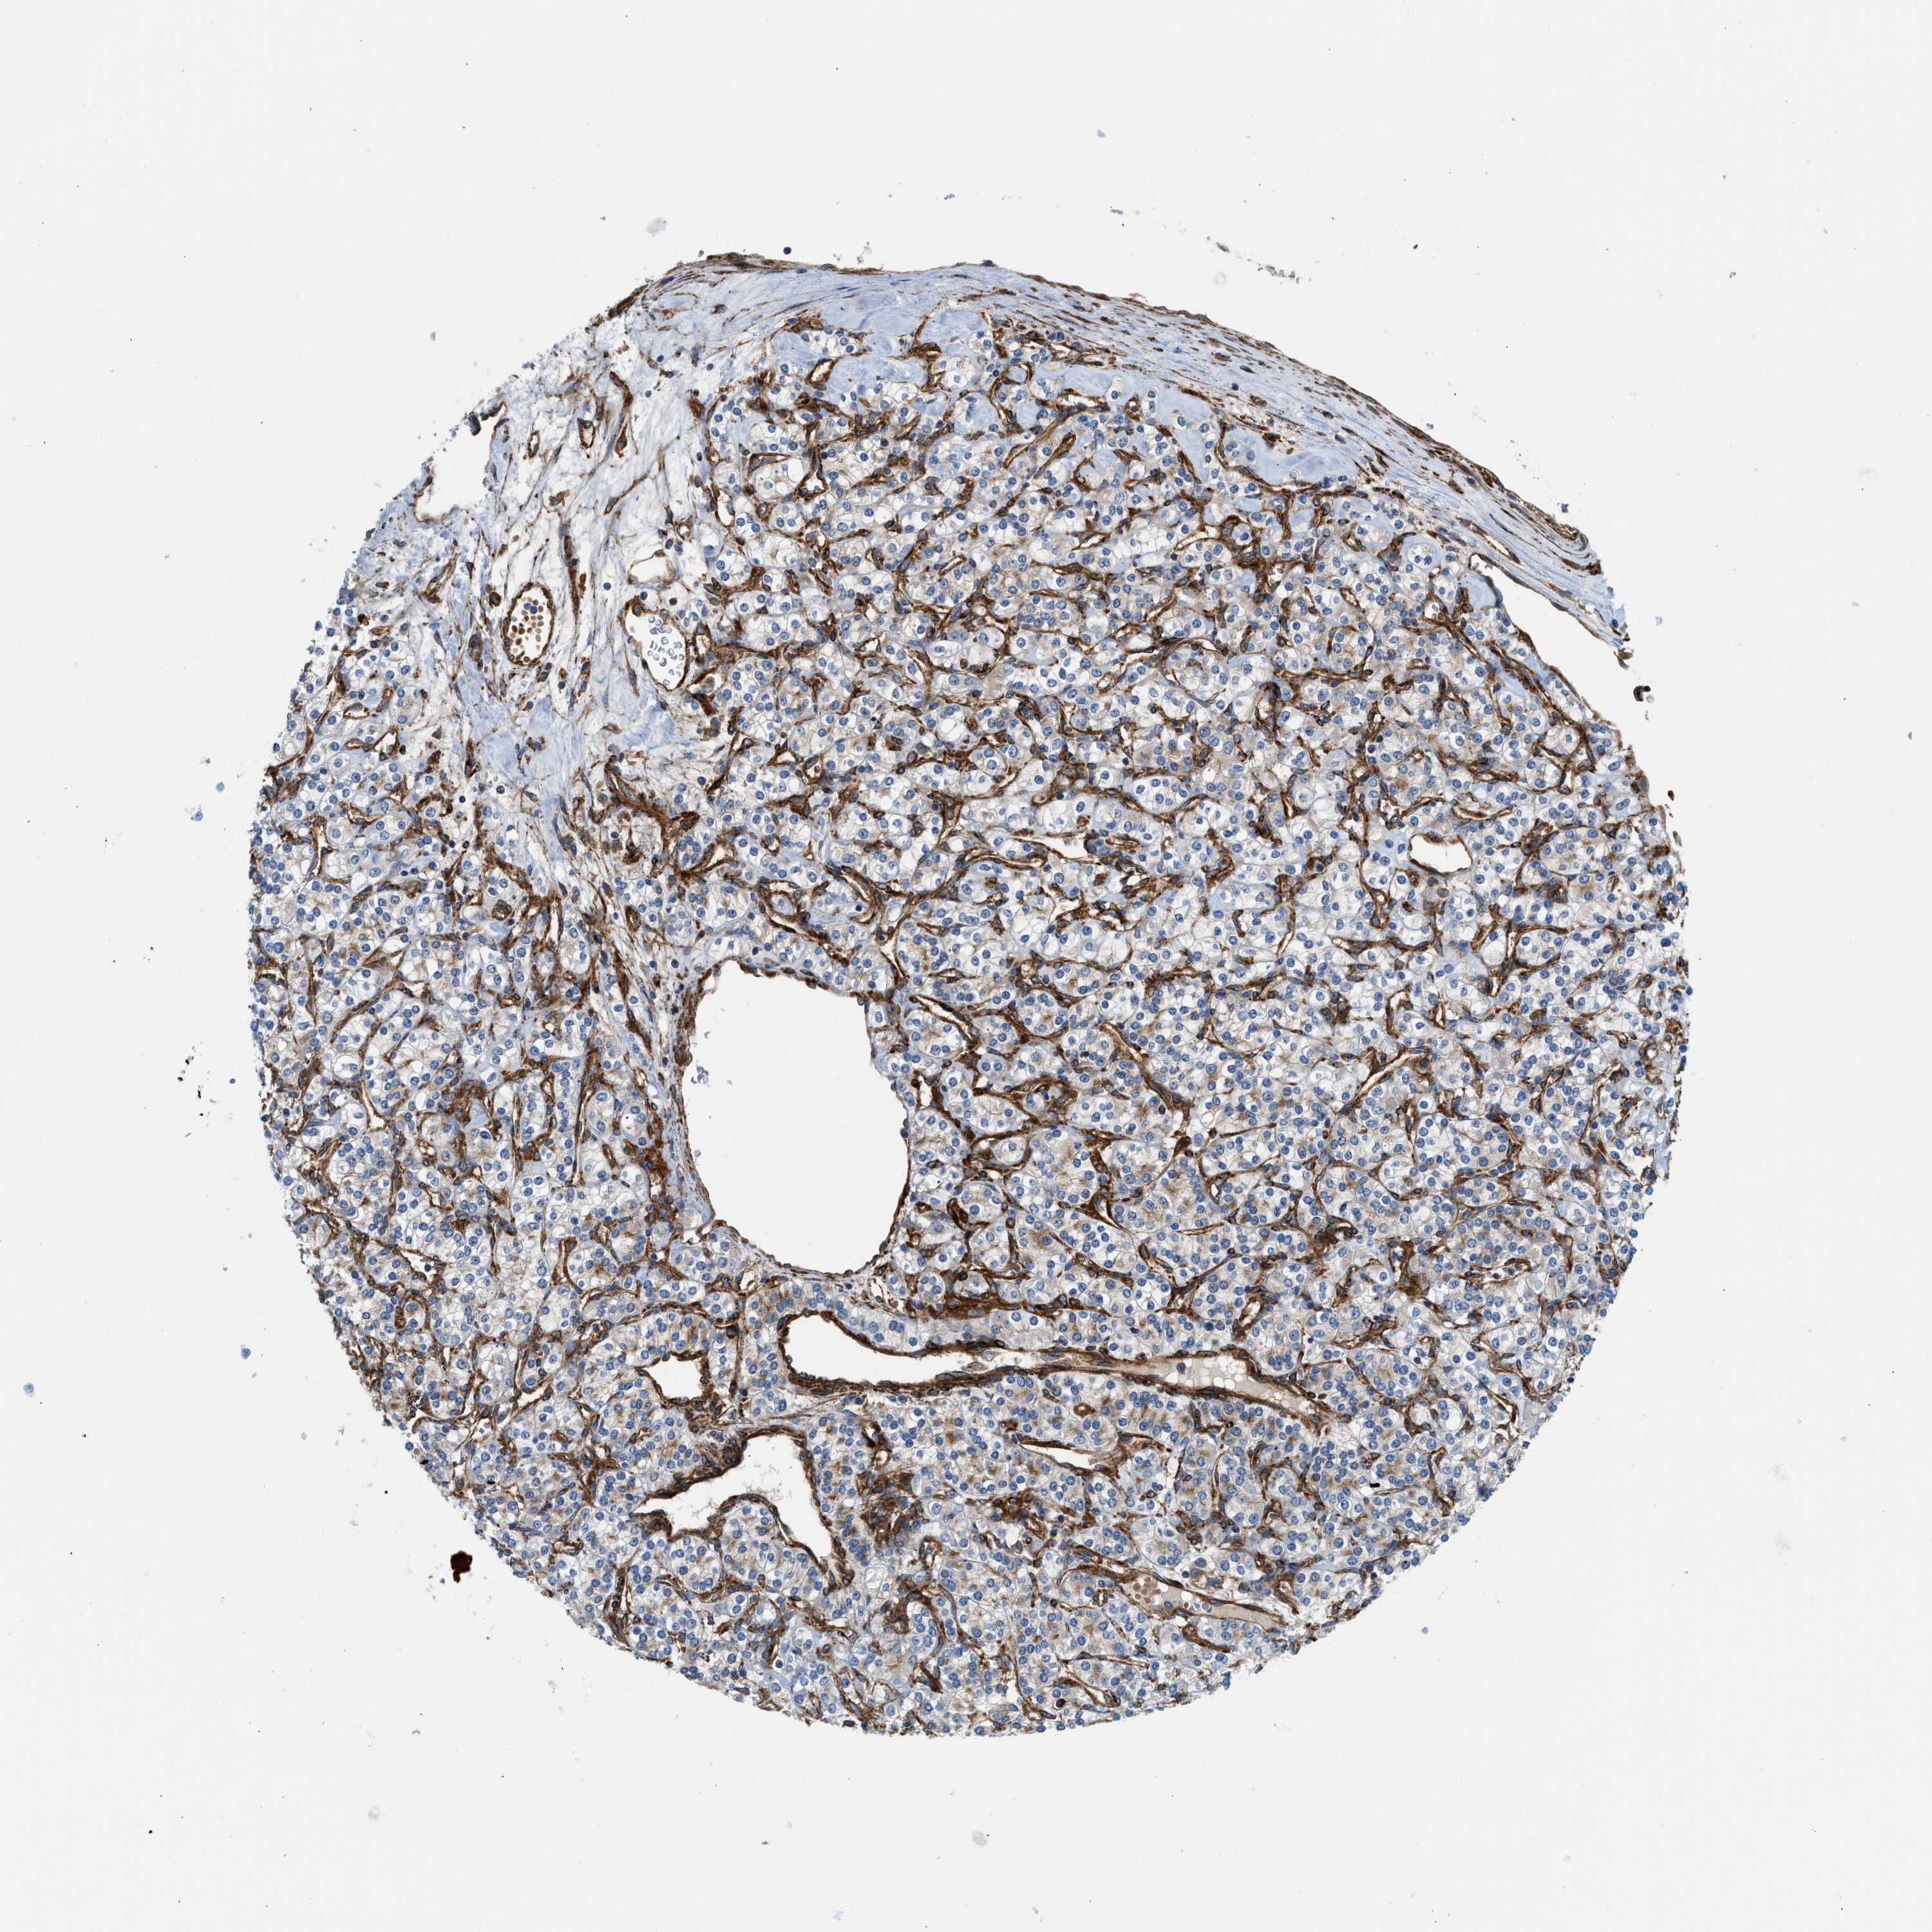

KIDNEY RENAL PAPILLARY CELL CARCINOMA (TCGA) - Interactive survival scatter ploti

The Survival Scatter plot shows the clinical status (i.e. dead or alive) for all individuals in the patient cohort, based on the same data that underlies the corresponding Kaplan-Meier plots. Patients that are alive at last time for follow-up are shown in blue and patients who have died during the study are shown in red.

The x-axis shows the expression levels (FPKM) of the investigated gene in the tumor tissue at the time of diagnosis. The y-axis shows the follow-up time after diagnosis (years). Both axes are complimented with kernel density curves demonstrating the data density over the axes. The top density plot shows the expression levels (FPKM) distribution among dead (red) and alive patients (blue). The right density plot shows the data density of the survived years of dead patients with high and low expression levels respectively, stratified using the cutoff indicated by the vertical dashed line through the Survival Scatter plot. This cutoff is automatically defined based on the FPKM cutoff that minimizes the p-score. The cutoff can be changed by dragging the vertical line or by entering a cutoff value in the square labeled "Current cut-off".

Under the Survival Scatter plot the p-score landscape (black curve; left axis) is shown together with dead median separation (red curve; right axis). Dead median separation is the difference in median mRNA expression between patients who have died with high and low expression, respectively. It is calculated as follows: median FPKM expression of dead patients with high expression - median FPKM expression of dead patients with low expression. This is intended to aid the user in visually exploring custom cutoffs and the associated p-scores and dead median separation.

Individual patient data is displayed and can be filtered by clicking on one or more of the category buttons on the top of the page. Categories describing expression level and patient information include: high, low, alive, dead, female, male and tumor stages. The scale of the x-axis can be toggled between linear and log-scale by clicking on the "x log" button. Mouse-over function shows TCGA ID, patient information and mRNA expression (FPKM) for each patient.

& Survival analysisi

Kaplan-Meier plots summarize results from analysis of correlation between mRNA expression level and patient survival. Patients were divided based on level of expression into one of the two groups "low" (under cut off) or "high" (over cut off). X-axis shows time for survival (years) and y-axis shows the probability of survival, where 1.0 corresponds to 100 percent.

HIP1 is not prognostic in Kidney Renal Papillary Cell Carcinoma (TCGA)

Best expression cut offi

Based on the FPKM value of each gene, patients were classified into two groups and association between prognosis (survival) and gene expression (FPKM) was examined. The best expression cut-off refers the FPKM value that yields maximal difference with regard to survival between the two groups at the lowest log-rank P-value. Best expression cut-off was selected based on survival analysis .

When clicking on this number, the vertical dashed line indicating cut-off, the interactive survival plot, and the Kaplan-Meier curve will be adjusted to show results based on the best expression cut-off.

: 6.95